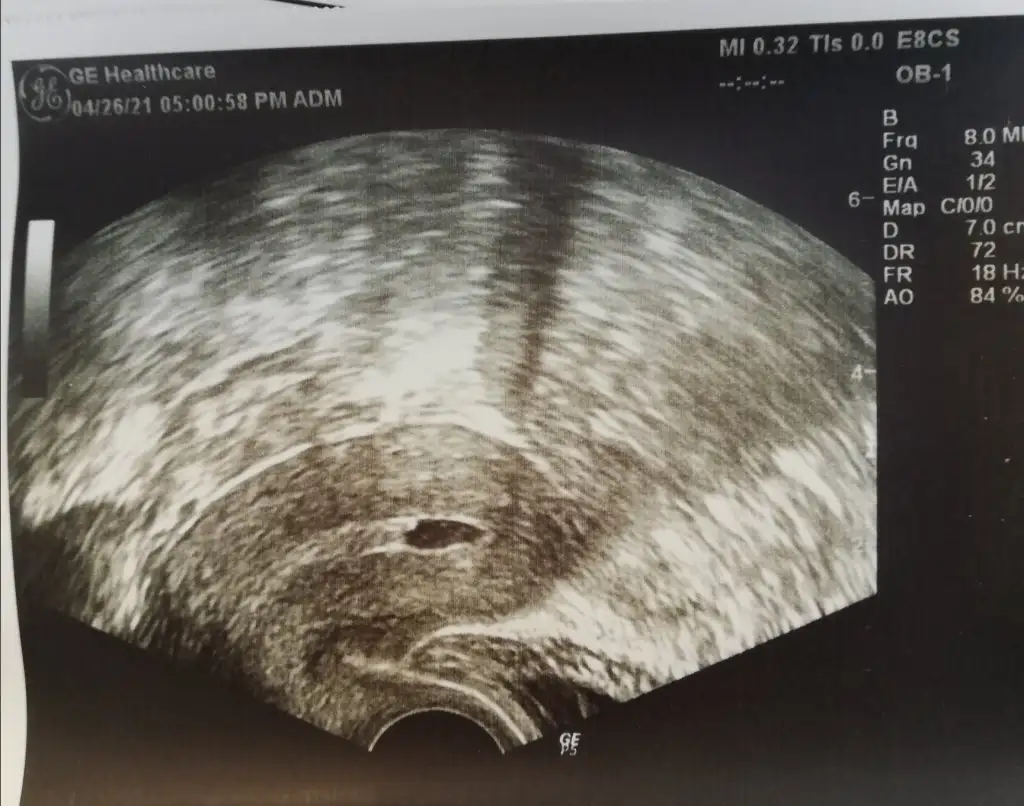

Kızlar günaydın. Embriyolarım hazır bekliyor ocakta opu olmuştum. Martta transfer olacakken polip var dedi iptal etti doktor ve histeroskopi oldum. Yine dinlendim yine başladım bu ay yine hazırlanıyorum ki dün gittiğimde sıvı olmuş belki yine polip vardır dedi yine histeroskopi yapacakmış. Ben yapacağımı şaşırdım. Daha transfer aşamasına bile gelemedim. Anlayan birisi varsa yorumlayabilir mi nedir bu😪 ogrtmn33 ogrtmn33 kuzucum ne yazık ki bende durumlar yine olumsuz😔

Eki Görüntüle 2835237 Kızlar günaydın. Embriyolarım hazır bekliyor ocakta opu olmuştum. Martta transfer olacakken polip var dedi iptal etti doktor ve histeroskopi oldum. Yine dinlendim yine başladım bu ay yine hazırlanıyorum ki dün gittiğimde sıvı olmuş belki yine polip vardır dedi yine histeroskopi yapacakmış. Ben yapacağımı şaşırdım. Daha transfer aşamasına bile gelemedim. Anlayan birisi varsa yorumlayabilir mi nedir bu😪 ogrtmn33 ogrtmn33 kuzucum ne yazık ki bende durumlar yine olumsuz😔